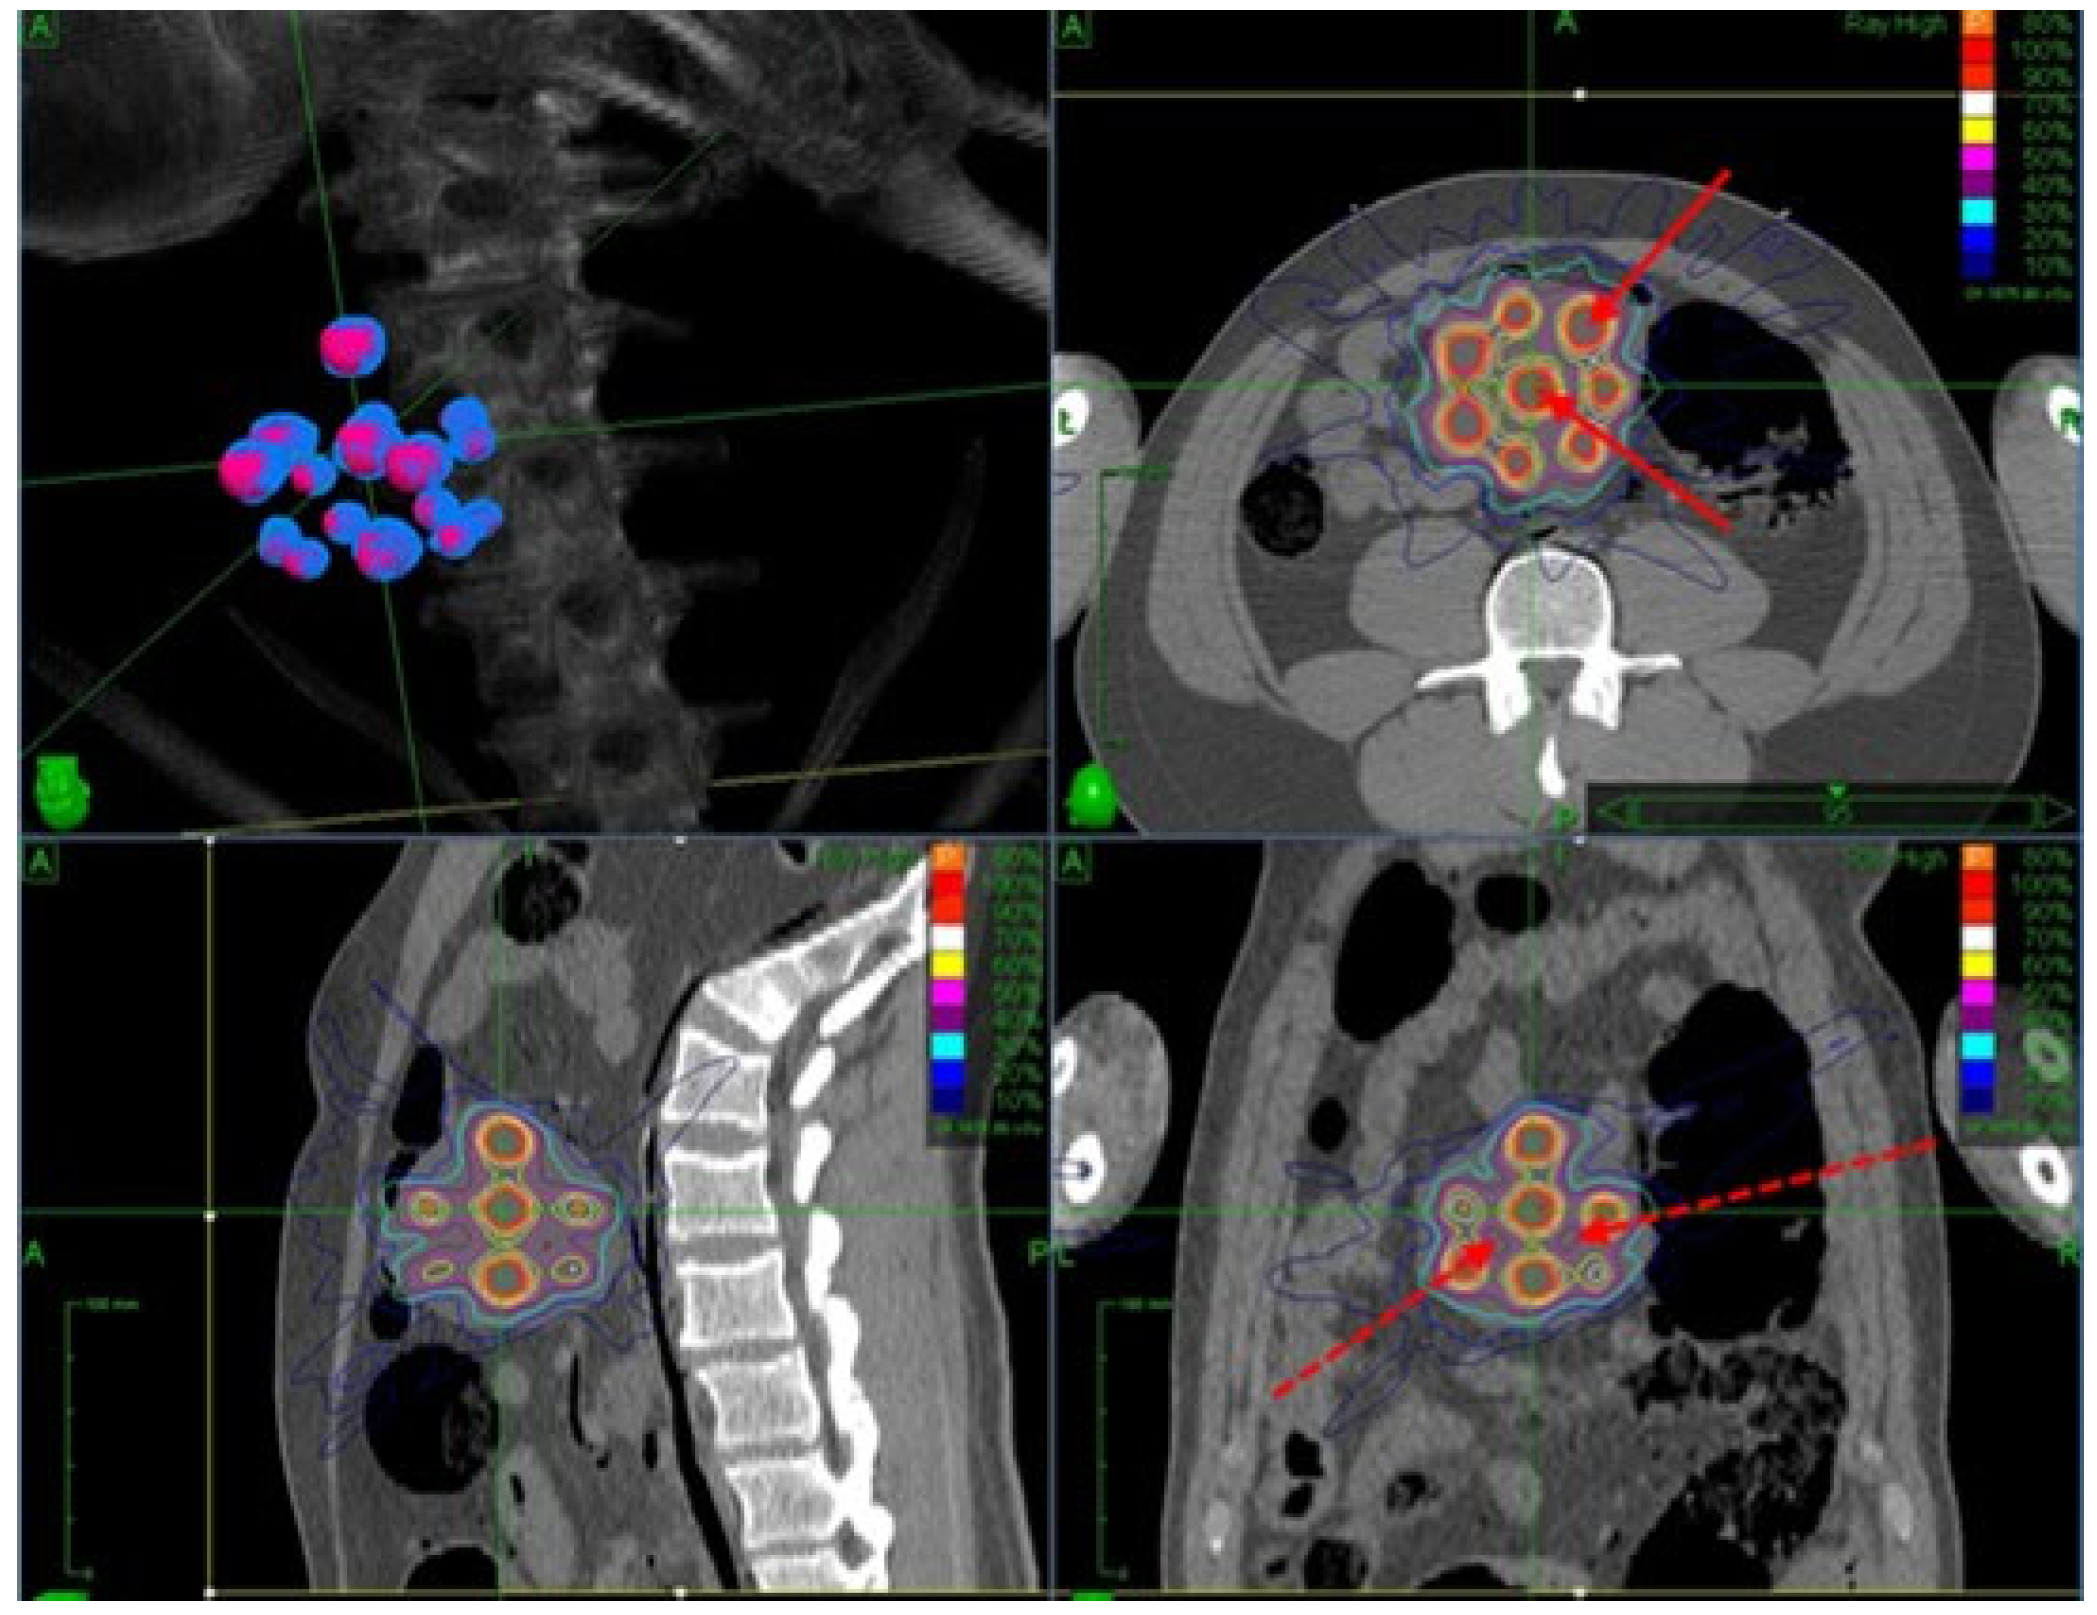

- LATTICE Therapy: This approach utilizes advanced treatment techniques (IMRT, VMAT, pencil beam scanning PRT, arc PRT, etc.) to conform peak doses to contoured high-dose volumes (vertices) [276,277]. LATTICE therapy mimics the dosimetric design of GRID therapy but offers more convenient delivery without requiring a physical grid. It also provides flexibility for customized OAR sparing through beam modulation [278]. Figure 6 shows a simulated LATTICE plan.